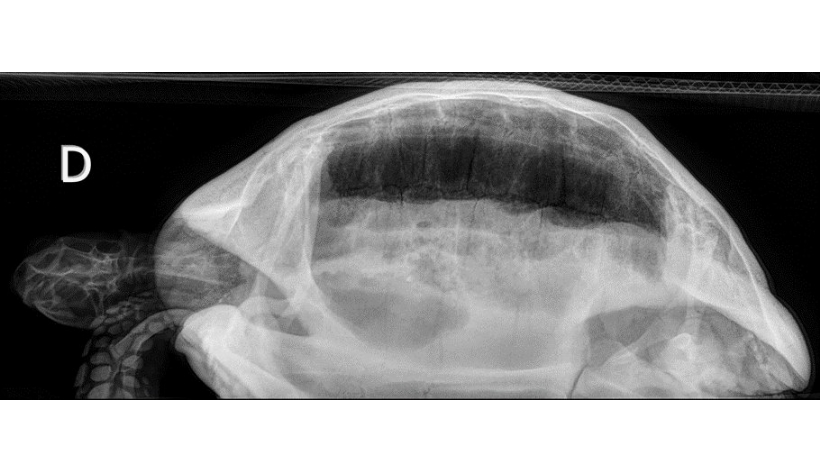

Mercredi 15 Octobre 2025 Animaux de compagnieCliché radiographique corps entier d'une tortue grecque de 25 ans présentée pour un bilan de santé dans un contexte de rhinite aiguë en vue latérale droite avec faisceau horizontal. Les champs pulmonaire sont de radio-opacité normale.

© Eléa Ceccantini-CHV OnlyVet